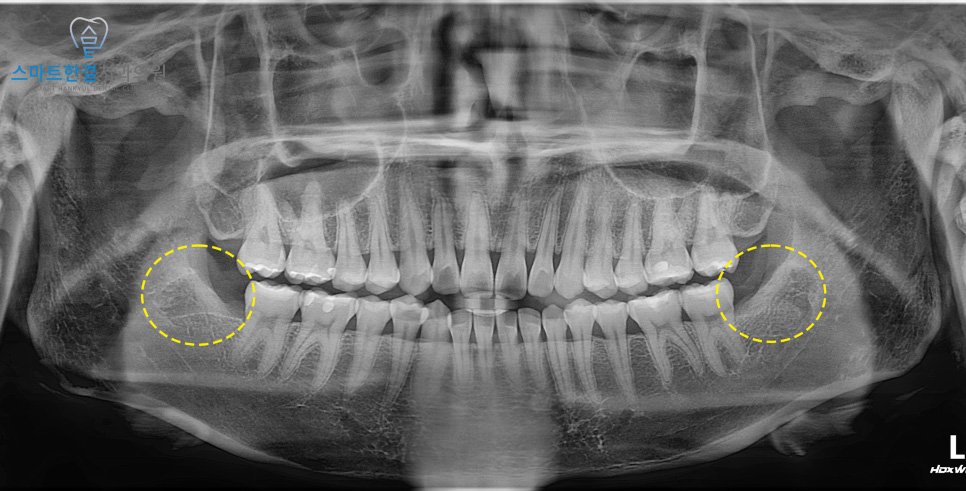

양쪽을 깨끗하게

발치 후 촬영한 사진인데요.

양쪽 사랑니 모두

비스듬히 누워 있었기 때문에

치아를 분할한 뒤 발치를 진행했어요.

오른쪽은 비교적 무리 없이

발치가 가능했지만,

왼쪽 사랑니는 뿌리가 휘어져 있어

치료 과정에서 뿌리가 부러질 가능성이 높아

더욱 세심한 접근이 필요했어요.

큰 문제 없이 부러지지 않고

깨끗하게 발치가 완료되었고,

환자분께서도 큰 통증 없이

마무리되셔서 만족해하셨어요.^^